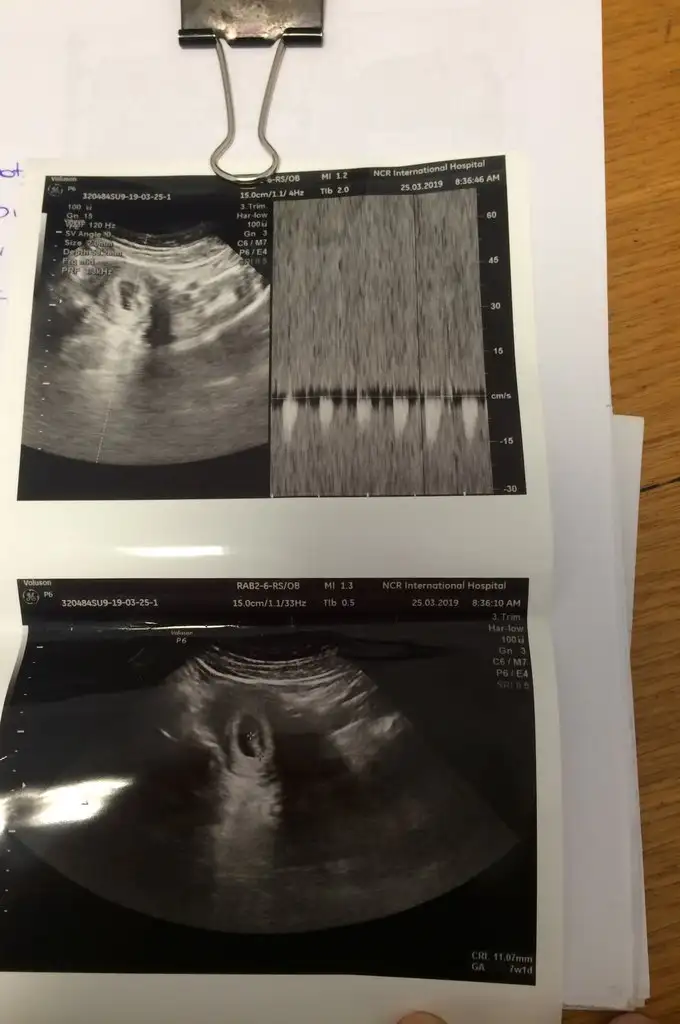

Benimde bugün kontrolüm vardı minik fasülyemi gördük kalp atışlarını duyduk çok şükür analiz yapan arkadaşlar dkda130 atıyordu ve ultrason görüntüsüne de bir bakıversinler ☺️

bugün 7+3 olduk canım 8. haftanın içindeyiz çok şükür. valla ben hala kollu bacaklı bir bebek görüntüsü göremiyorum ultrason kağıdımda :-) hatta eşim de gidiyoruz geliyoruz çocuk hala 1 cm nasıl büyüyecek bu diyor :KK70: doktorda birşey söylemedi sanırım beklediğim görüntü için henüz erken, bir sonraki randevuya 1 ay sonra gelirsin dedi 11 haftalık olacağız o zaman kolunu da görürüm bacağını da diye düşünüyorum :KK36: sen nasılsın ne kadarlık oldunuz

iyi ki o heyecan var çok şükür rabbime :KK36: ben en çok kalbinin durmasından korkuyordum doktora ilk onu sordum kalbini görebiliyor musunuz diye banada gösterdi hala atıyor pıt pıt çok şükür, artık biraz daha rahat içim.. amiiin canım çok amin :KK200: ama bu 1 ay nasıl geçecek onu bilmiyorum tabi :)

bende ilk önce aynı şeyi sormuştum kalbi atıyor mu ilk onu söyleyin demiştim, şükür ki atıyordu inşallahta atmaya devam ediyordur. canım senin usg görüntünle bide bi üstte yeni usg görüntüsü atan arkadaşa baktım benimki sizinkilerden çok farklı neden ki anlamadım gitti , yani duruş ve yapı olarak farklı sizin ki yuvarlak gibi benim ki salatalık gibi :)